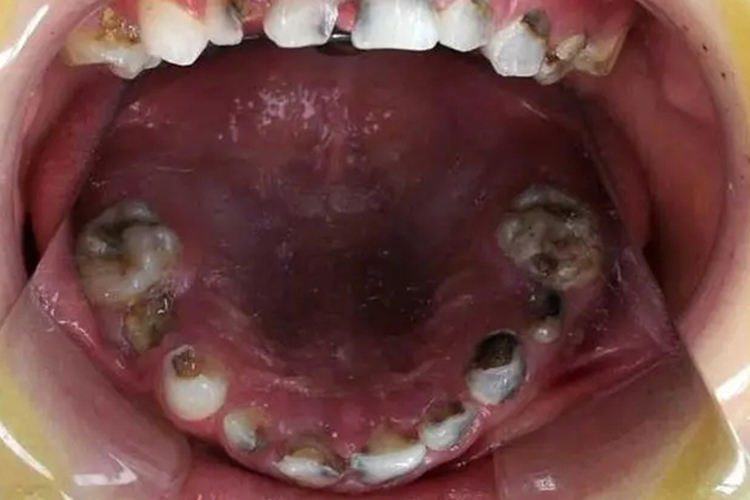

儿童牙齿发黑烂掉可有牙齿松动、牙体缺损明显、颌面部肿痛、张口困难等症状。

儿童牙齿发黑烂掉常见于儿童龋病的深龋,龋洞深大,达牙本质深层,牙体缺损明显,病变牙本质质地较软;当食物嵌塞入龋洞中或患牙遇冷、热、酸、甜、化学刺激时可出现疼痛,去除刺激后症状立即消失。如果病变继续发展,则可能会出现颌面部肿痛、张口困难、高热等全身症状。

对于儿童牙齿发黑烂掉的治疗,需尽快去除腐质,对破坏严重、牙髓已经暴露需要大量治疗且预后很差的乳牙可拔除,拔除后视牙齿替换情况做间隙保持或正畸治疗。治疗后的缺损牙体可用银汞合金、复合树脂、玻璃离子等材料修复,也可用预成金属冠修复。